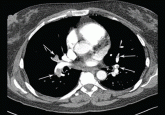

ArticleA 51-year-old woman with dyspneaAuthor:Andrew D. Goldberg, MDPublish date: August 1, 2013Her symptoms began 4 days ago. She appears uncomfortable and anxious, her pulse is over 160, and her respirations are 40. What is going on?Read More